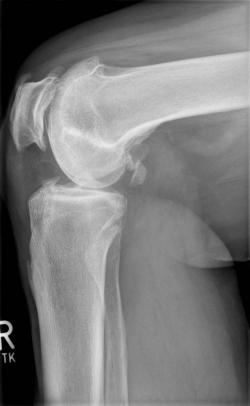

X-rays can be used to reliably diagnose the extent of joint wear. In the case of high-grade gonarthrosis, for example, the joint space and the formation of jagged edges (bone attachments, "osteophytes") as well as axial malalignment can be detected. If additional damage to the internal structures of the knee is suspected, ultrasound examination (sonography) or magnetic resonance imaging (MRI) can help clarify the situation.

Example X-ray images before and after implantation of a Persona knee prosthesis with robot.

| a) präoperative Röntgenbilder des kranken Knies in 2 Ebenen | |